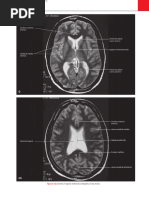

CB

AV: arteria vertebral

CB: cisterna bulbar

AV

CP: cisterna pontina

AB: arteria basilar

CM: cisterna magna

AB

CP

CM

4V

CPC

4V: cuarto ventrculo

CPC: cisterna pontocerebelosa

par V

par VI

par VII

par VIII

par IX

CVS

CVS: cisterna vermiana superior